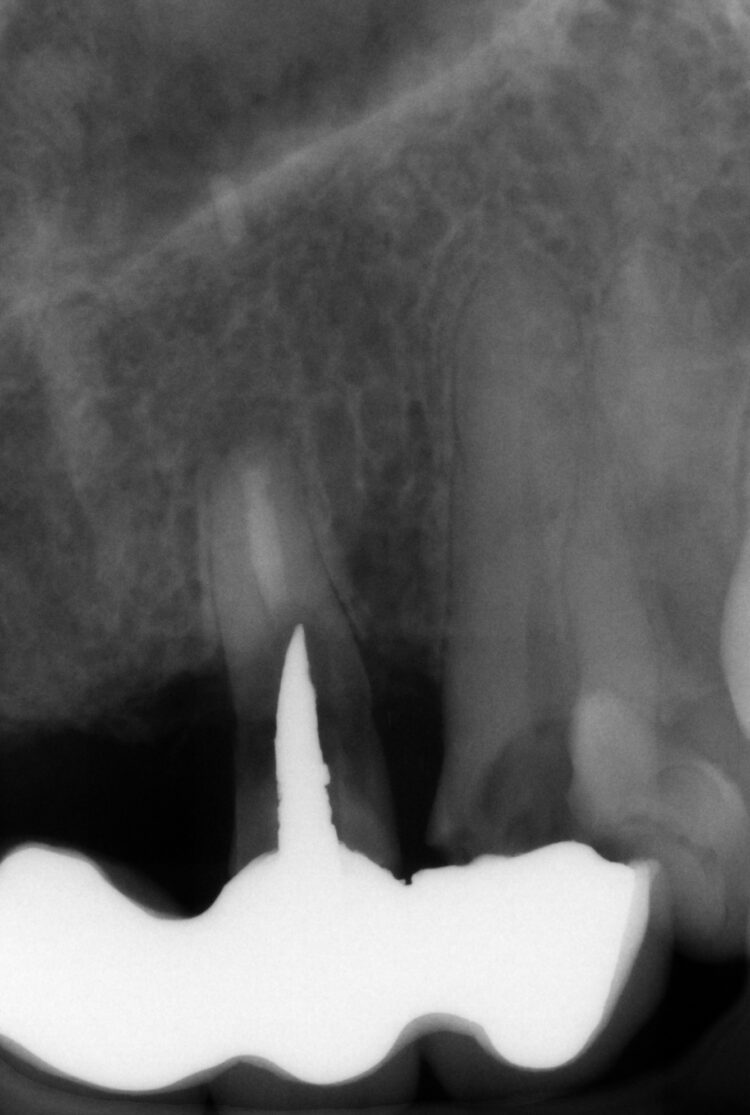

Despite using all the available examination tools, it was still challenging to assess the level of damage to the teeth under the metal ceramic bridge, because the prosthetic material obstructed the x-ray. It was confirmed that two teeth were decayed and fractured, but it was not possible to confidently diagnose the UR2.

Having identified the UL3 as needing extraction, this provided an ideal site for immediate implant placement. The existing root was large with limited bone available around it, so it was crucial to ensure appropriate implant selection and precise placement for good stability.

This new conical connection provides confidence that an optimal emergence profile will be achieved with the restoration, which is crucial when working in the aesthetic zone. The 3.3mm diameter implants were chosen; while wider implants are generally preferred, this case required a balance between utilising the available bone and adhering to natural structures, necessitating the use of narrower implants.

The two 3.3mm diameter Tapered Pro Conical implants were then placed through the guide at the pre-determined positions, angles and depths. Both implants achieved an insertion torque above 30Ncm.